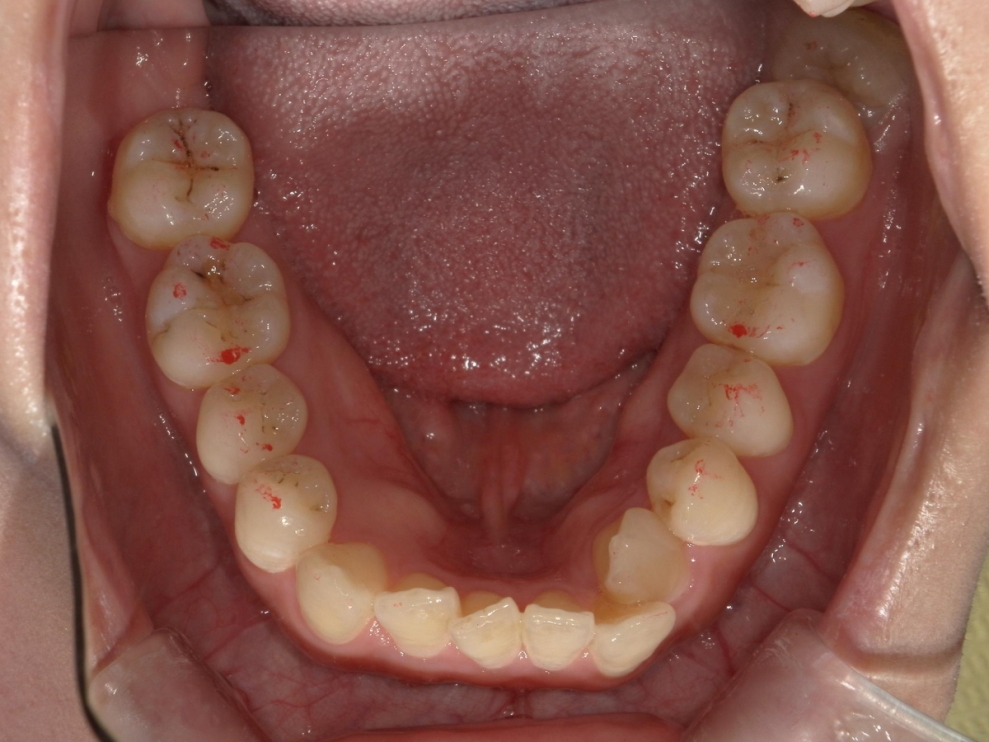

BEFORE

AFTER